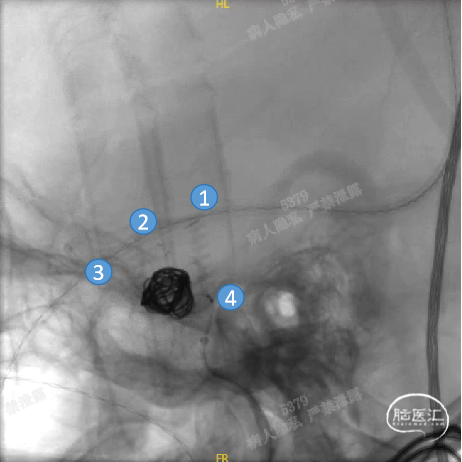

Headway™ 27 156cm微导管内输送FRED 4518血流导向密网支架,系统远端精准定位于预计着陆区以远3-5mm,回撤微导管原位释放支架,头端锚定在颈内末端处。

正位

①输送导丝头端

②支架远端扩口显影点

③有效段起始点

④支架近端扩口显影点

确认支架远端定位于计划位置,预估近端可完全覆盖动脉瘤颈,且锚定距离充足。继续平衡释放系统,确保支架整体充分打开且贴壁良好后,解脱支架。

工作角度

①支架远端扩口显影点

②有效段螺旋显影丝

③支架近端扩口显影点

造影确认,载瘤动脉通畅、支架远端分支血流通畅、支架贴壁良好、动脉瘤内造影剂滞留。